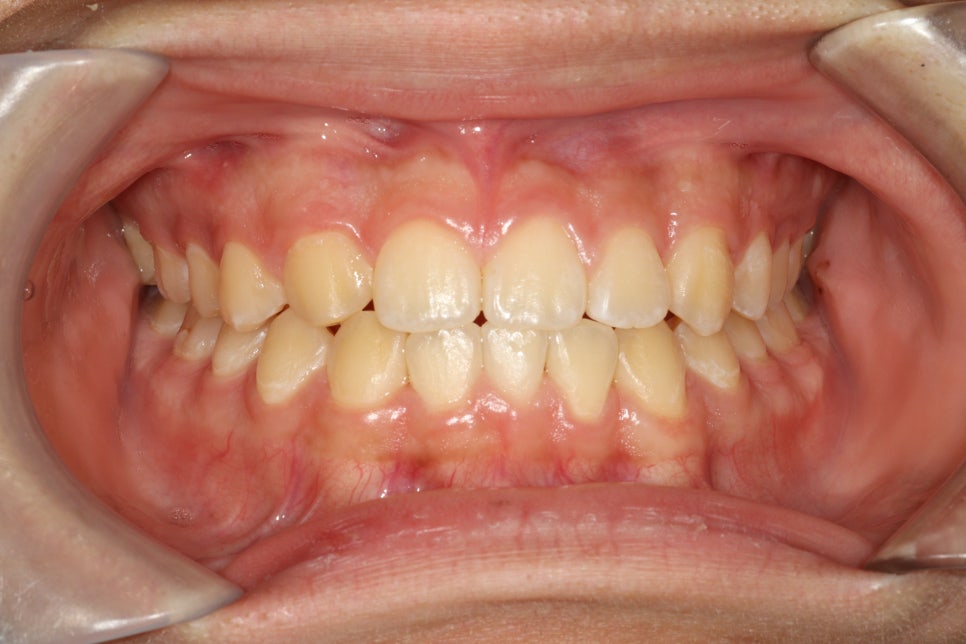

최종 치료가 마무리된 모습입니다.

얼굴 중심선과 위 치아의 중심선이 일치하고, 그 위의 사진을 보면 위 아래 치아의 중심선도 일치하고 있습니다.

알고보면 양쪽 치아의 구성 및 배열, 교합이 다른것이 보이지만,

대충 보시면 어디가 결손이고, 어디를 발치했는지 모르실 수 있습니다.